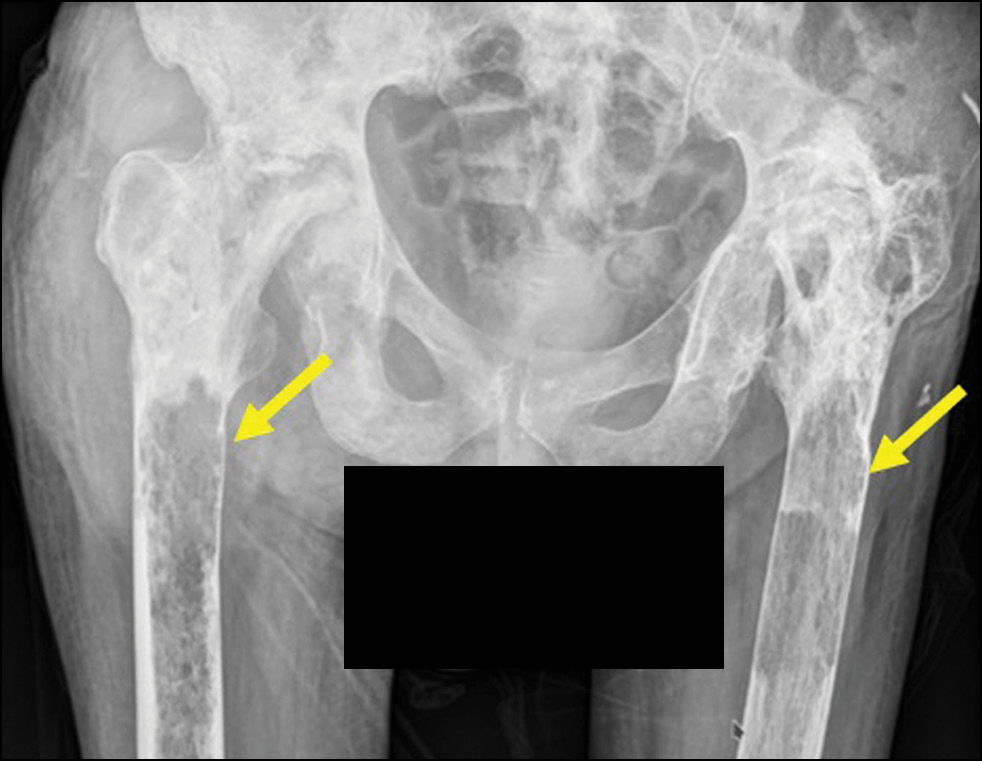

Рис. 5. Рентгенограмма тазобедренных суставов в прямой проекции. Головки бедренных костей разрушены, вертлужные впадины деформированы, суставные щели не прослеживаются. Выраженная перестройка видимых костей с наличием неоднородных участков уплотнения, разнокалиберных (до 4 см) участков разрежения без чётких контуров. Резкое истончение коркового слоя проксимального диафиза бедренных костей (указано стрелкой).

Fig. 5. X-ray of the hips in direct projection. The femoral heads are destroyed, the acetabulum is deformed, and the articular crevices are not visible. Pronounced restructuring of visible bones with the presence of heterogeneous areas of compaction, various-sized (up to 4 cm) areas of rarefaction without clear contours. Sharp thinning of the cortical layer of the proximal diaphysis of the femoral bones (indicated by the arrow).